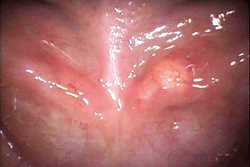

b:左側ワルトン管の開口部付近に黄色の腫脹が見られる

図❶ a、b 初診時の口腔内写真

口腔内所見:左側口底部に20㎜程度の発赤を伴うび漫性腫脹を認め、唾液腺開口部付近の粘膜下に、わずかに黄色を呈する粟粒大の硬固物を認めた(図❶)。